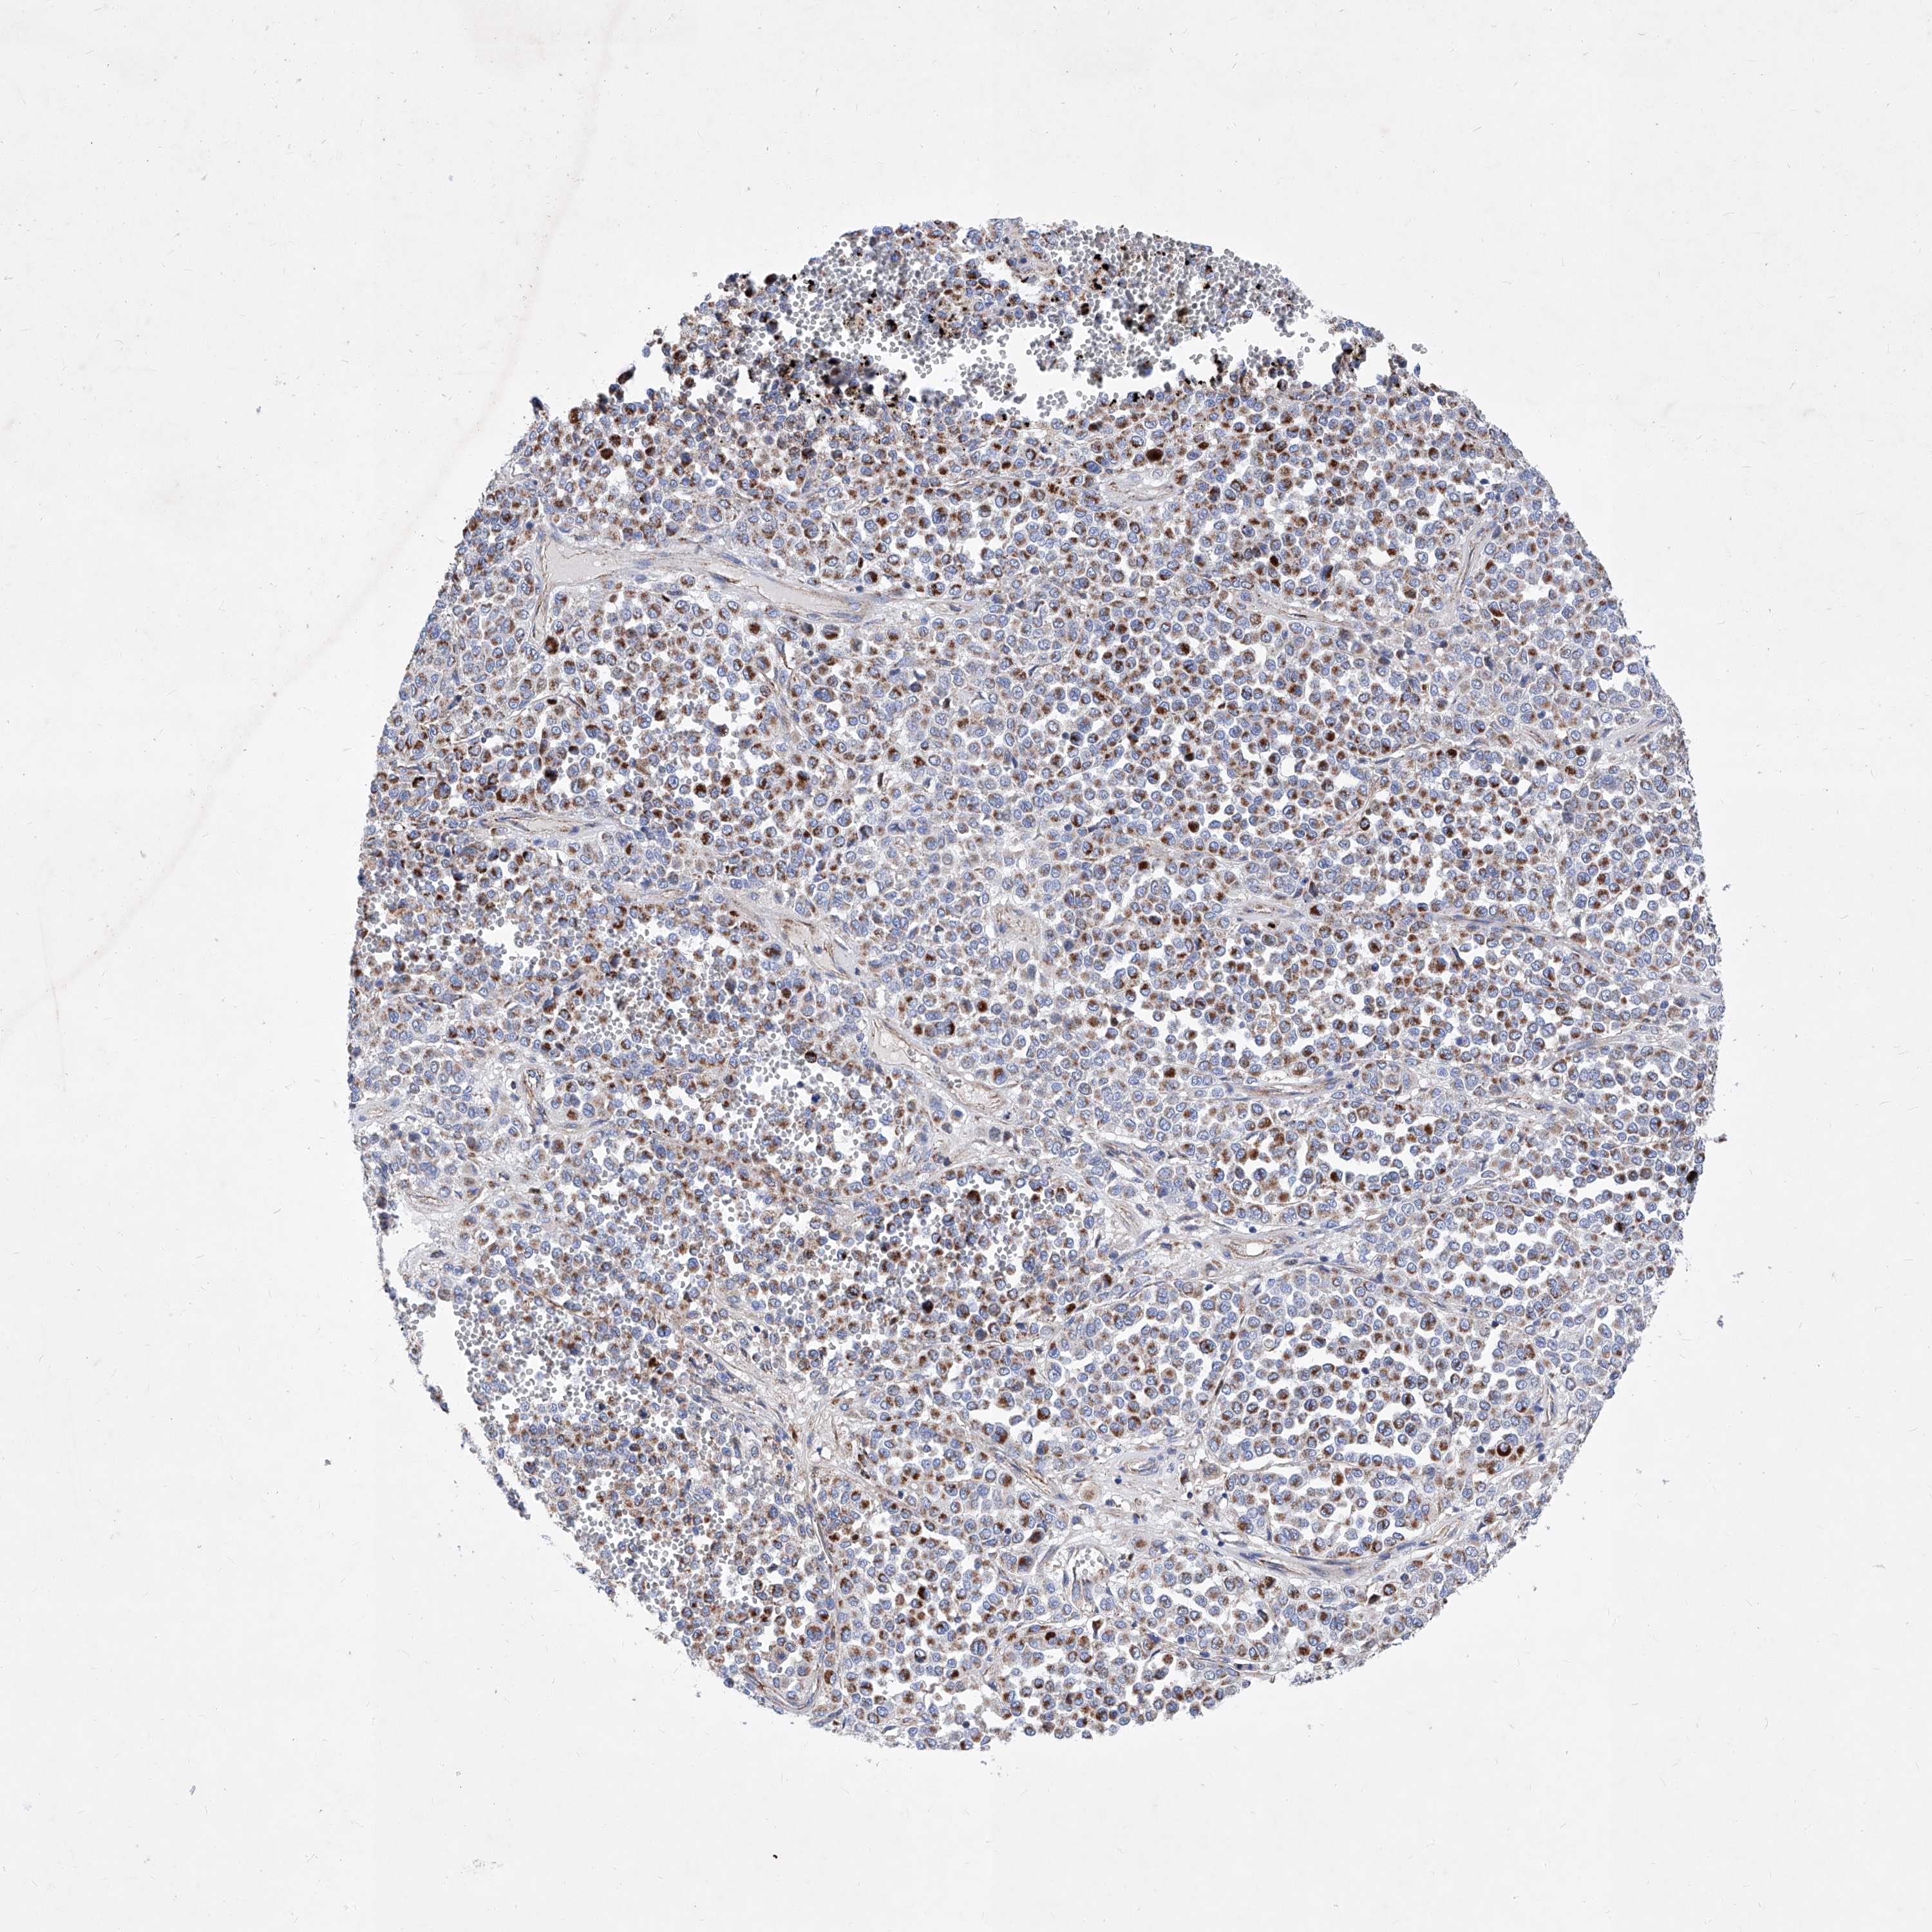

MELANOMA - Protein expressioni

A mouse-over function shows sample information and annotation data. Click on an image to view it in a full screen mode. Samples can be filtered based on level of antibody staining by selecting one or several of the following categories: high, medium, low and not detected. The assay and annotation is described here.

Note that samples used for immunohistochemistry by the Human Protein Atlas do not correspond to samples in the TCGA dataset.

Antibody stainingi

Antibody staining in the annotated cell types in the current human tissue is reported as not detected, low, medium, or high, based on conventional immunohistochemistry profiling in selected tissues. This score is based on the combination of the staining intensity and fraction of stained cells.

Each image is clickable and will lead to virtual microscopy that enables deeper exploration of all samples and also displays staining intensity scores, fraction scores and subcellular localization as well as patient and tissue information for each sample.

Antibody HPA031469

Staining

High

Medium

Low

Not detected

Intensity

Strong

Moderate

Weak

Negative

Quantity

>75%

75%-25%

<25%

None

Location

Nuclear

Cytoplasmic/membranous

Cytoplasmic/membranous,nuclear

Malignant melanoma, NOS

Malignant melanoma, Metastatic site